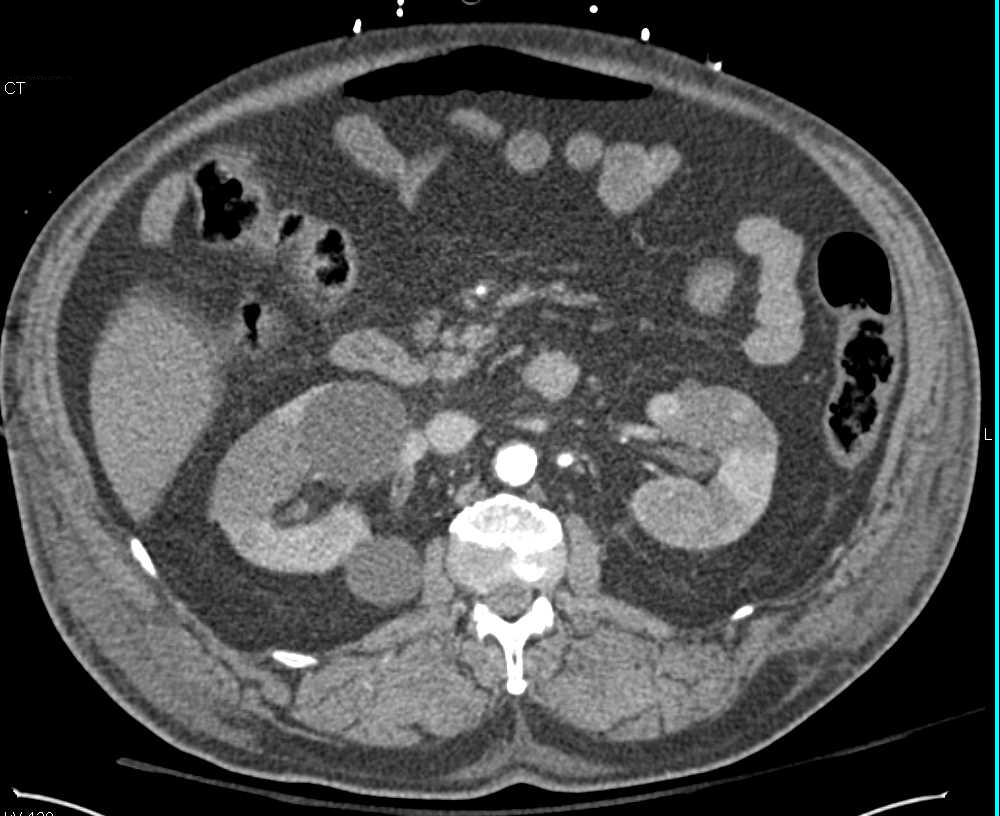

Bilateral Renal Infarcts